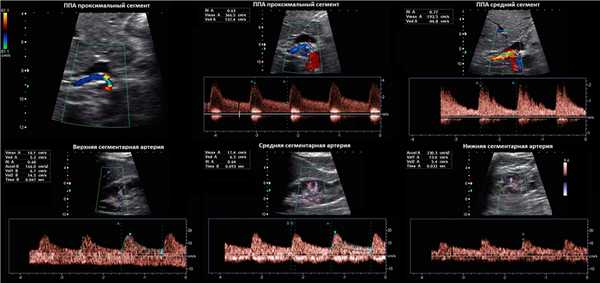

Рисунок. Пациентка 60-ти лет с рефрактерной артериальной гипертензией. PSV на брюшной аорте 59 см/сек. В проксимальном отделе ППА при ЦДК элайзинг (1), PSV значительно повышен 366 см/сек (2), RAR 6,2. В среднем сегменте ППА при ЦДК элайзинг, PSV 193 см/сек (3), RAR 3,2. На сегментарных артериях без существенного увеличения времени ускорения: верхняя — 47 мс, средняя — 93 мс, нижняя — 33 мс. Заключение: Стеноз в проксимальном отделе правой почечной артерии.